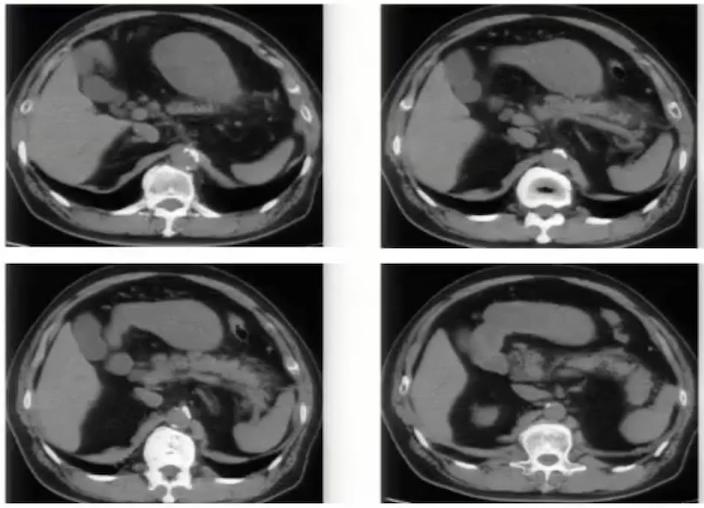

下腔静脉畸形 以双下腔静脉畸形及左下腔静脉畸形最常见。

左下腔静脉畸形为肾下段下腔静脉在主动脉的左侧上升,与左肾静脉汇合,通过主动脉前方与右肾静脉汇合,并在此水平上形成正常的右下腔静脉。

双下腔静脉畸形表现为左下腔静脉终止于左肾静脉,通过主动脉前方汇入右下腔静脉。

图11:腹主动脉两侧均有下腔静脉影,左侧下腔静脉向上与左肾静脉汇合后,在腹主动脉前方绕行,移行为右侧下腔静脉